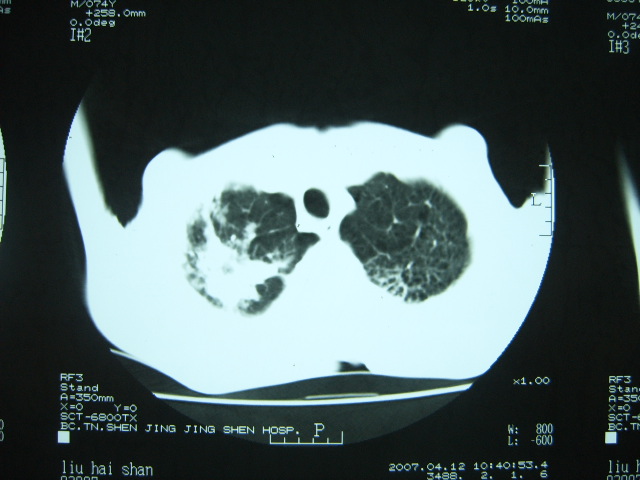

男74岁,咳嗽,寒战,低烧。有糖尿病史。

两肺慢性炎症伴脓肿形成,不除外继发霉菌感染。

1、左下肺肺脓肿,合并霉菌球形成?.2、双肺陈旧性病灶.3、右上肺病灶警惕瘢痕癌,建议定期复查.

1.双肺结核

2.左下肺脓肿

两肺结核,左下肺大片实变,内见空洞性病变,壁不规则,结合糖尿病史,考虑:结核性?霉菌性?建议结合实验室检查或治疗后复查。